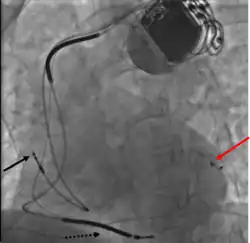

Permanent pacing with an implantable pacemaker involves transvenous placement of one or more pacing electrodes within a chamber, or chambers, of the heart, while the pacemaker is implanted under the skin below the clavicle. The procedure is performed by incision of a suitable vein into which the electrode lead is inserted and passed along the vein, through the valve of the heart, until positioned in the chamber. The procedure is facilitated by fluoroscopy which enables the physician to view the passage of the electrode lead. After satisfactory lodgement of the electrode is confirmed, the opposite end of the electrode lead is connected to the pacemaker generator.

CRT devices have at least two leads, one passing through the vena cava and the right atrium into the right ventricle to stimulate the septum, and another passing through the vena cava and the right atrium and inserted through the coronary sinus to pace the epicardial wall of the left ventricle. Often, for patients in normal sinus rhythm, there is also a lead in the right atrium to facilitate synchrony with the atrial contraction. Thus, the timing between the atrial and ventricular contractions, as well as between the septal and lateral walls of the left ventricle can be adjusted to achieve optimal cardiac function.

A pacemaker may be implanted whilst a person is awake using local anesthetic to numb the skin with or without sedation, or asleep using a general anesthetic.[25] An antibiotic is usually given to reduce the risk of infection.[25] Pacemakers are generally implanted in the front of the chest in the region of the left or right shoulder. The skin is prepared by clipping or shaving any hair over the implant site before cleaning the skin with a disinfectant such as chlorhexidine. An incision is made below the collar bone and a space or pocket is created under the skin to house the pacemaker generator. This pocket is usually created just above the pectoralis major muscle (prepectoral), but in some cases the device may be inserted beneath the muscle (submuscular).[26] The lead or leads are fed into the heart through a large vein guided by X-ray imaging (fluoroscopy). The tips of the leads may be positioned within the right ventricle, the right atrium, or the coronary sinus, depending on the type of pacemaker required.[25] Surgery is typically completed within 30 to 90 minutes. Following implantation, the surgical wound should be kept clean and dry until it has healed. Some movements of the shoulder within a few weeks of insertion carry a risk of dislodging the pacemaker leads.[25]